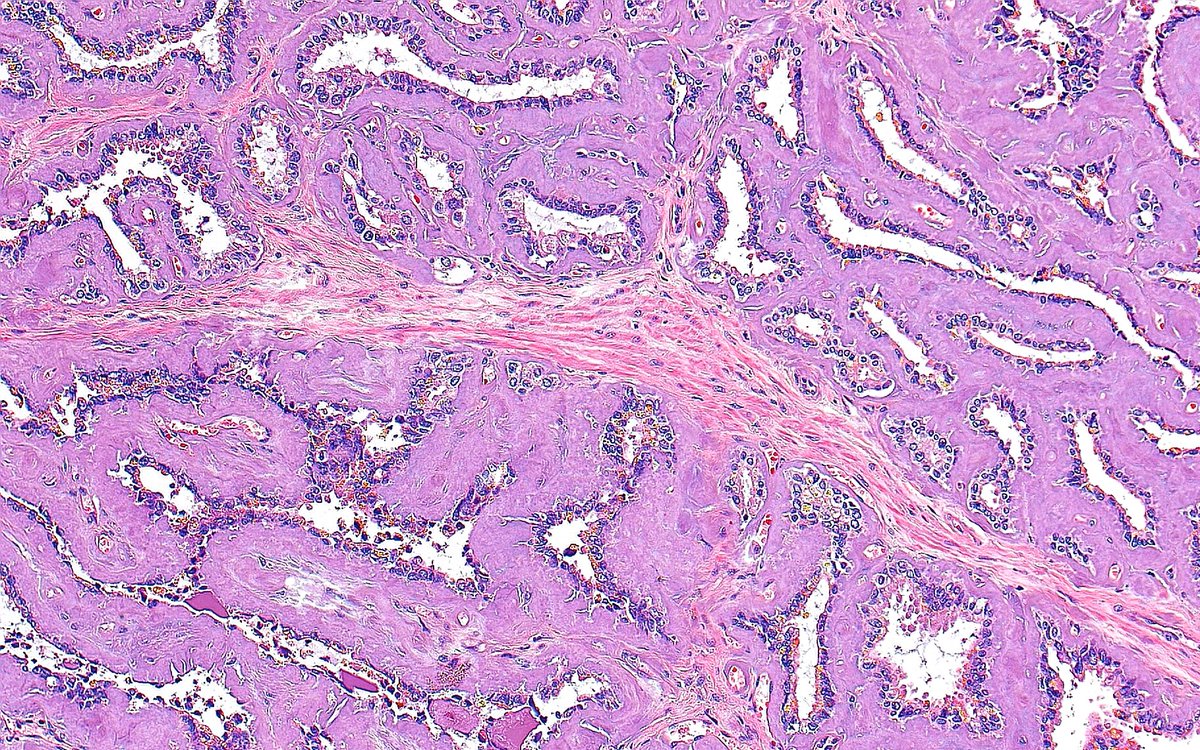

π¬πΈ "Papillary Capillaries" ~ Fibrovascular core of a papillary urothelial carcinoma with multiple capillaries ~ #GUpath #Pathology #Bladder #PathArt

0

15

67